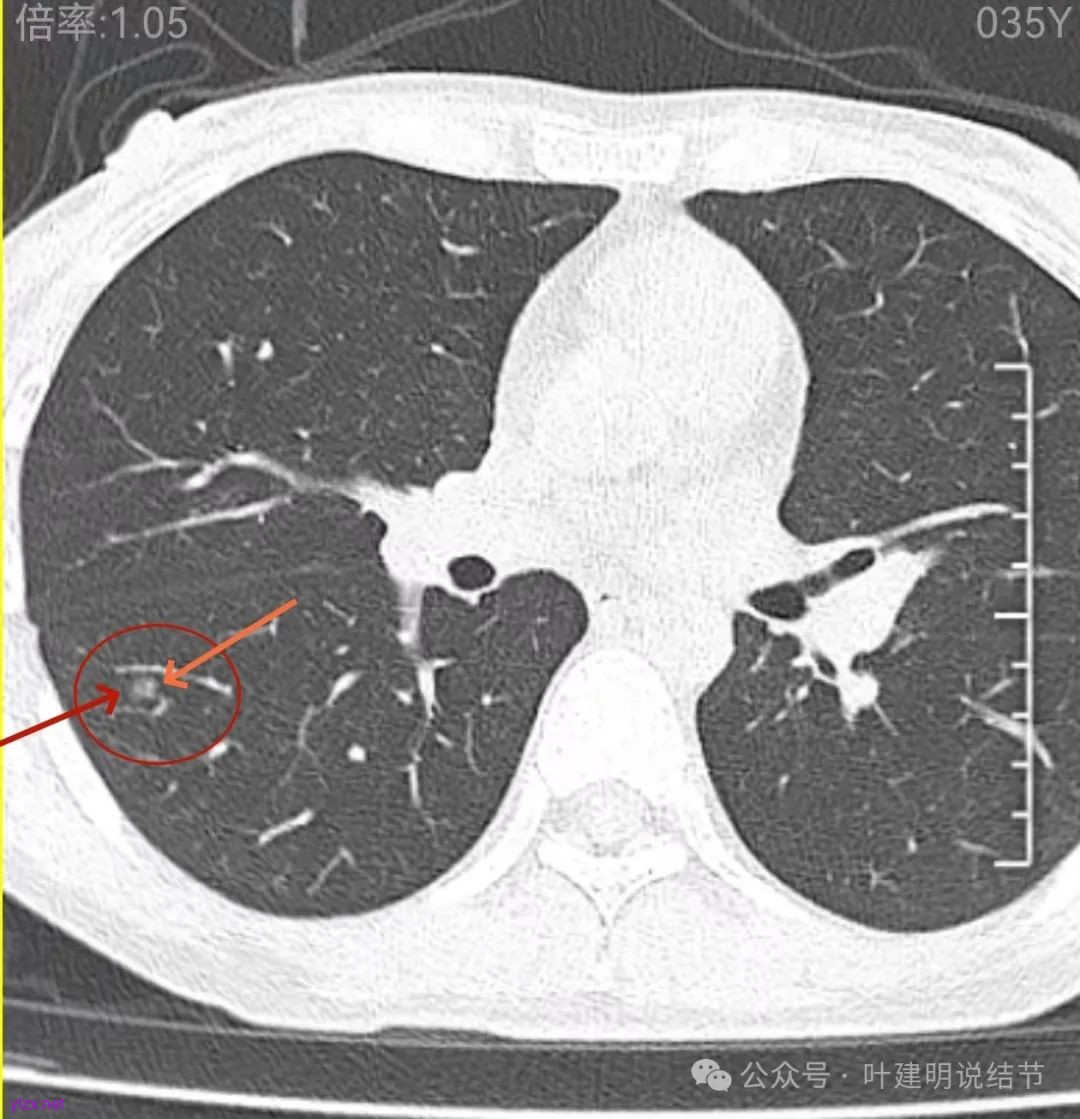

先来看2024年12月的影像:

表面不平,轮廓较清,有血管进入,边缘略显毛糙。

病灶内有少许偏实性成分,与血管关系较为密切,局部似有浅分叶的样子。

两肺多发结节,左侧黄色标注的考虑是肺泡上皮增生可能性大;蓝色的考虑肺泡上皮增生或者少许慢性炎可能性大;右侧红色宽起来并带有红色箭头的这处是主病灶,偏混合密度,整体轮廓较为清楚,边缘显得毛糙,从2024年12月份的来看,要考虑是肿瘤范畴,原位癌或者微浸润性腺癌可能性较大,也不能完全排除不典型增生。但是在2022年的时候,这个病灶的边上也有一个实性的微小结节,如果只看2022年的,这么小的实性结节,又比较圆,表面也显得较为光滑,是要考虑良性的,当然太小了需要动态观察。回头再重新来看2024年底的,发现绿色箭头所指的这个微小实性的较2022年几乎没有变,去仔细寻找2022年的,发现当时在实性结节旁边也有密度很淡的一点磨玻璃影(也可能真的就是一处,只是扫描不够薄,密度的变化有些突兀而已),而到了2024年12月份,实性微小这处没有明显变化,但是原来很淡的磨玻璃变成了混合磨玻璃,范围也明显扩大。所以总体来看右肺下叶这处是考虑恶性的,而且从磨玻璃结节角度来讲,还是生长比较快的,就是说还是有一定风险的。加上左侧还有两处也是磨玻璃持续存在,虽然边缘轮廓显模糊一点,但多年以后也可能仍然要变成原位癌或者微浸润性腺癌之类的东西。通盘考虑以后,我倾向于右侧近期单孔胸腔镜下微创局部切除,左侧随访观察,等到有进展并风险增加再来考虑处理。意见供参考!